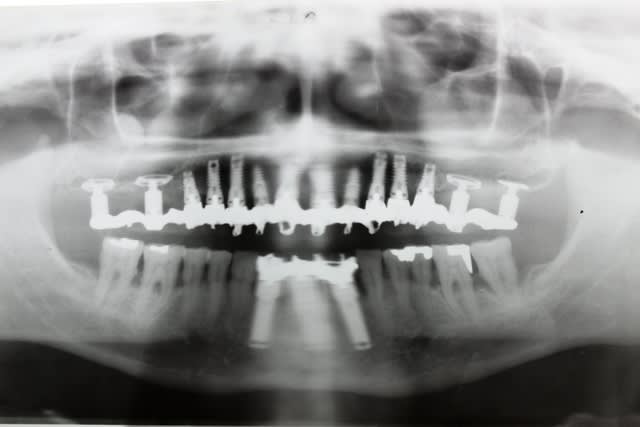

Le dentascan de la mandibule pour que vous compreniez mieux la difficulté...quais impossible de la considérer en cylindres même en déplaçant le NDI vous n avez aucune hauteur exploitable... Même des lame de Likow n y passent pas et les sous périostés sont interdits en Europe

J ai perdu mes deux foutus cylindres et ai dû les remplacer par deux double disk...et changer les deux mono disk du secteur droit

Et oui l implanto basale n est pas non plus un long fleuve tranquille